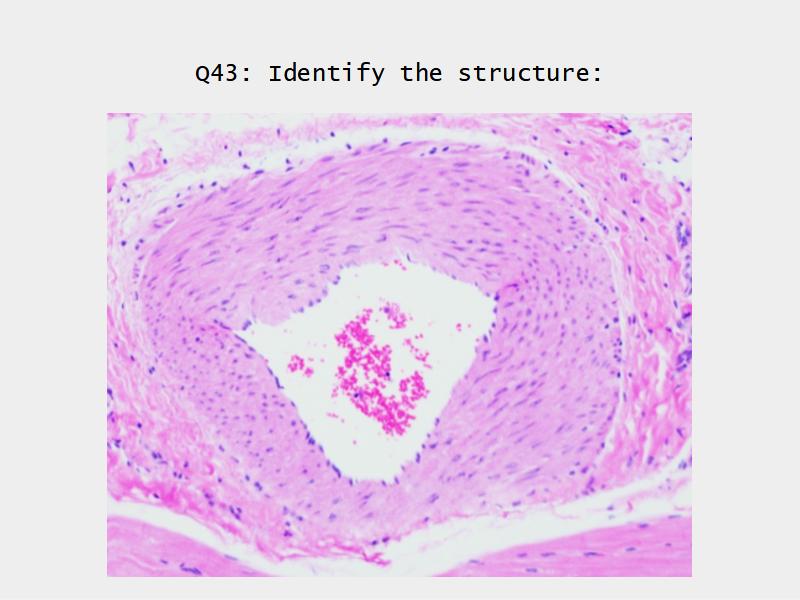

The cardiovascular system needs to be connected to the respiratory system.Path of O2 and CO2

- List complete

- With layers

- And cells

- And function of each